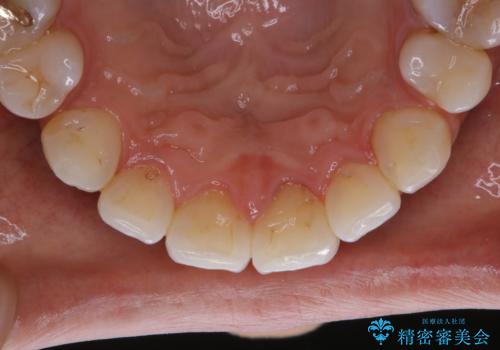

- フロスが以前よりも通りずらくなり、クリーニングしてほしいとのことでした。歯科医院でのクリーニングは3年ぶりとのことです。PMTC60分コースを行いました。

歯科医院で行なわれる専門家による徹底した歯面清掃をPMTC(Professional Mechanical Tooth Cleaning)といいます。専用の機器とフッ化物入り研磨剤を使用して、歯みがきで落とせない歯石や磨き残したプラークを中心に総ての歯面の清掃と研磨を行ない、齲蝕や歯周病になりにくい環境を整えます。

歯石が溜まると、歯と歯の間が埋め尽くされてしまい、デンタルフロスが通りずらくなったり、通せなくなります。

かなり上手に磨ける人でも、セルフケアだけで、虫歯や歯周病予防を行うことには限界があります。

また、定期的に歯科医院にてクリーニングやチェックをしていると口腔内の変化があった場合の、早期発見につながります。口腔内の状態により、個人差はありますが約3か月を目安にPMTCを行うことがおすすめです。